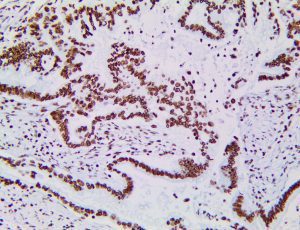

The first cytokines released are interleukin 1β (IL-1β) and tumor necrosis factor-α (TNF-α), which attract a variety of circulating white blood cells (WBCs) to the infection site, including neutrophils, monocytes, macrophages, and natural killer (NK) cells. This response, along with the antipathogenic chemicals released by these cells (i.e., complement), comprise the innate immune response. These cells directly attack the invading pathogen and also release additional cytokines, chief among them interleukin-1 and 6 (IL-6). IL-6 is essential for invoking the adaptive immune response, which calls T-cells, B-cells, and T helper (Th) cells to the infection site. IL-6 also stimulates further recruitment, proliferation and activation of macrophages.

It is the ICU physician who is most likely to witness one of the deadliest manifestations of the abnormal immunological response, the cytokine storm syndrome (CSS). This response is also referred to by some as the cytokine release syndrome (CRS). CSS is characterized by continuous activation and expansion of macrophage and lymphocyte populations, which secrete large amounts of cytokines, causing the cytokine storm. This massive cytokine release is akin to hemophagocytic lymphohistiocytosis (HLH) disease, a syndrome characterized by initial unchecked and persistent activation of cytotoxic T lymphocytes and NK cells.